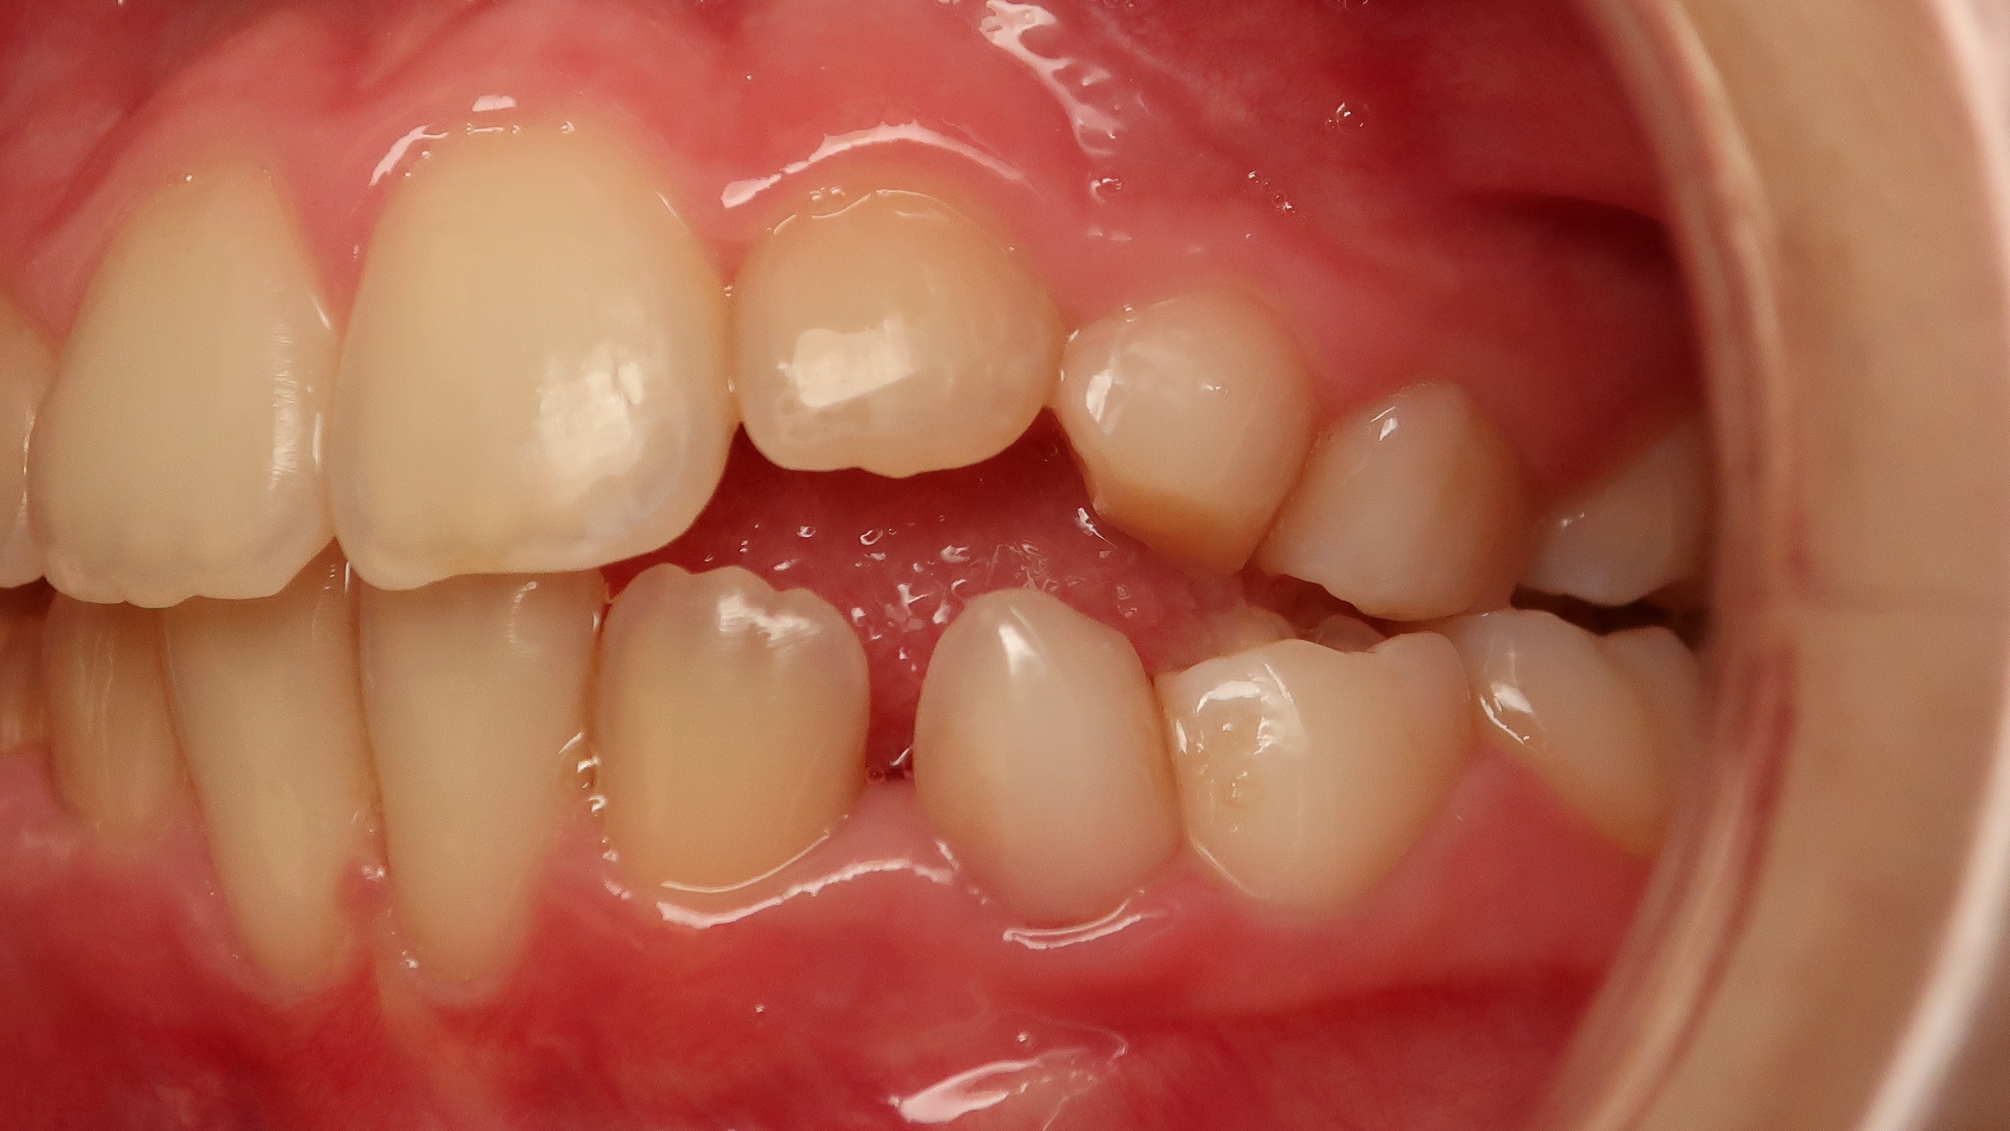

surveillance évolution de la dentition en cours

bilan début et en cours de traitement